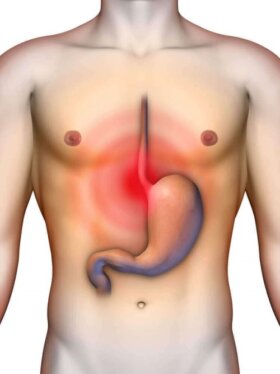

위산 역류를 완화하는 홈메이드 제산제 몇 가지를 소개한다. 위산 역류를 계속 달고 살면 귀찮고 짜증이 난다. 위산 역류는 식도의 마지막…

복부 팽만을 줄여주는 가정 요법 5가지를 소개한다. 복부 팽만은 장기의 노폐물과 가스가 쌓여 복부가 팽창하는 증상을 말한다. 극심한 더부룩함, 부어오름, 배 속에…